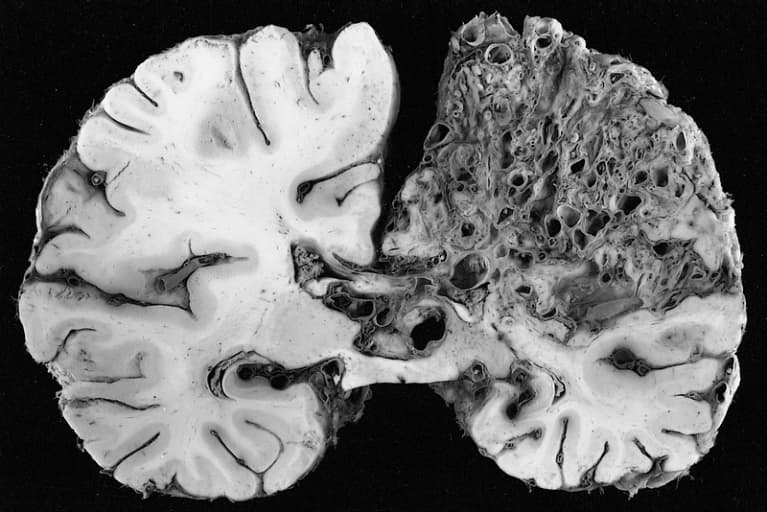

A cerebral arteriovenous malformation (cerebral AVM, CAVM, cAVM, brain AVM, or BAVM) is an abnormal connection between the arteries and veins in the brain—specifically, an arteriovenous malformation in the cerebrum. The most frequently observed problems related to a cerebral arteriovenous malformation (AVM) are headaches and seizures, cranial nerve afflictions including pinched nerve and palsy, backaches, neckaches, and nausea from coagulated blood that has made its way down to be dissolved in the cerebrospinal fluid. Perhaps 15% of the population at detection are asymptomatic. Other common symptoms are a pulsing noise in the head, progressive weakness, numbness and vision changes as well as debilitating, excruciating pain. In serious cases, blood vessels rupture and cause bleeding within the brain (intracranial hemorrhage). In more than half of patients with AVM, this is the first symptom. Symptoms due to bleeding include loss of consciousness, sudden and severe headache, nausea, vomiting, incontinence, and blurred vision, amongst others. Impairments caused by local brain-tissue damage on the bleed site are also possible, including seizure, one-sided weakness (hemiparesis), a loss of touch sensation on one side of the body and deficits in language processing (aphasia). Ruptured AVMs are responsible for considerable mortality and morbidity. AVMs in certain critical locations may stop the circulation of the cerebrospinal fluid, causing it to accumulate within the skull and giving rise to a clinical condition called hydrocephalus. A stiff neck can occur as the result of increased pressure within the skull and irritation of the meninges. A cerebral AVM is an abnormal anastomosis (connection) between the arteries and veins in the human brain and are most commonly of prenatal origin. In a normal brain, oxygen-enriched blood from the heart travels in sequence through smaller blood vessels going from arteries, to arterioles and then capillaries. Oxygen is removed in the capillaries to be used by the brain.